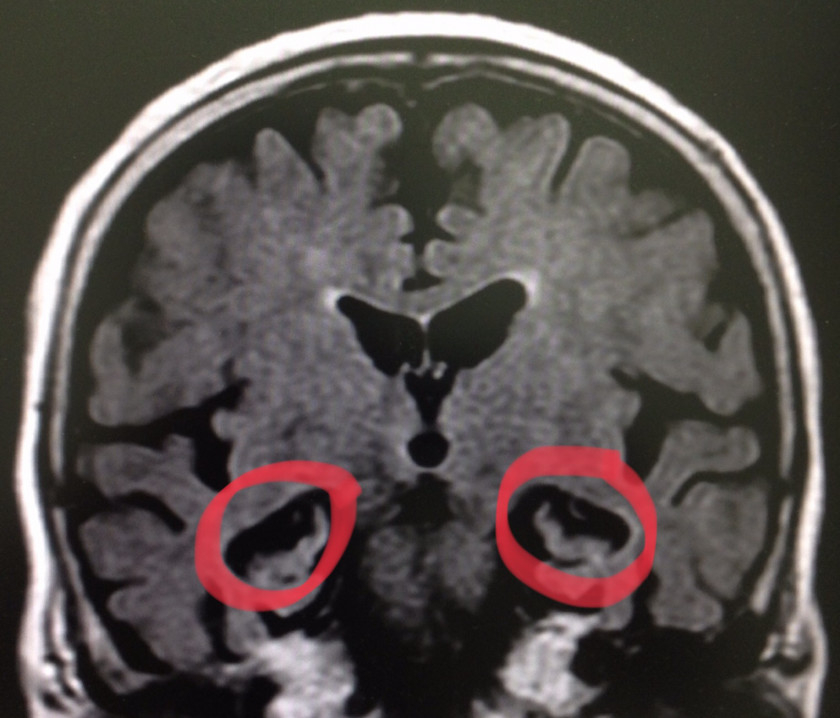

2018/10/31 レビー小体型認知症+「他 認知症」合併症例

パーキンソン病と◯年も前に診断されています。幻視、せん妄も認めています。前医では、抗認知症薬が処方されていました。

受診時の認知機能テスト他から判断するに、どのような効果が出ているのか❓・・・。テストの点数はヒトケタ、遅延再生は全く得点できず。時計や図形も・・・。そして、結果を裏付けるようなMRI結果。

高度な側頭葉内側の萎縮は純粋なレビーのそれとは異なります。

とても、とても、酵素を阻害したくらいで、記憶が改善するなんて状況では無かったのです。記憶に関与する細胞は激減、「記憶装置」は見事に破壊されているのですから。しかも、錐体外路症状は非常に強く、どんどん日常生活動作のレベルが低下する中、どのように対処していくべきか。

ムダな抗認知症薬は中止しましたが、今後、いかに運動機能を維持するか❓

レビー小体を消し、ニューロン再生ができる日は❓

パーキンソン病と◯年も前に診断されています。幻視、せん妄も認めています。前医では、抗認知症薬が処方されていました。受診時の認知機能テスト他から判断するに、どのような効果が出ているのか❓・・・。テストの点数はヒトケタ、遅延再生は全く得点できず。時計や図形も・・・。そして、結果を裏付けるようなMRI結果。